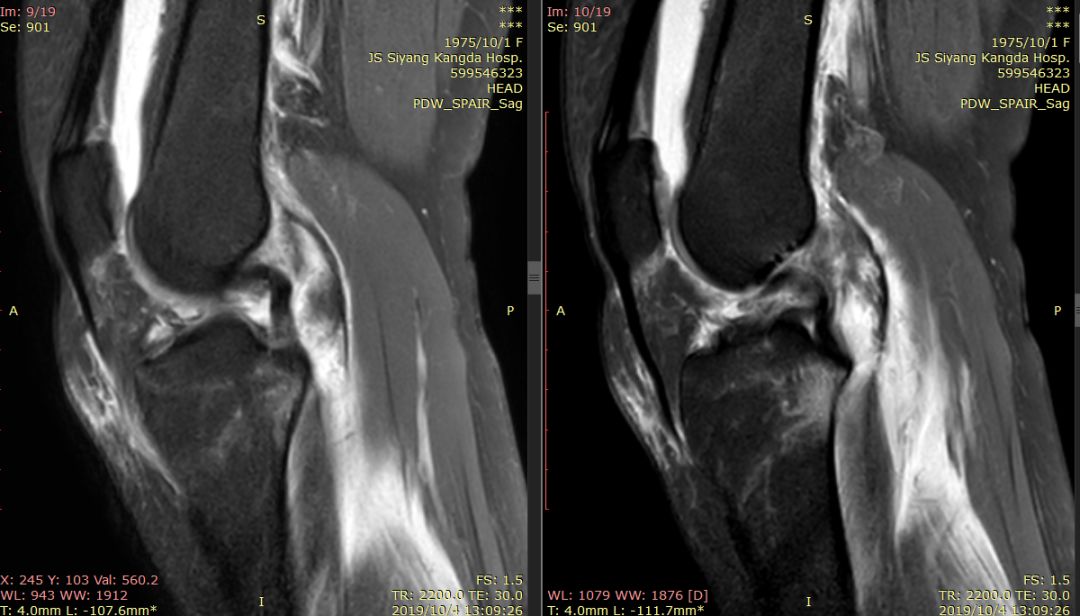

前交叉韧带“消失”

外侧半月板后角“消失”

下图横断面的标线标记的是左下图,为外侧半月板的桶柄样撕裂移位